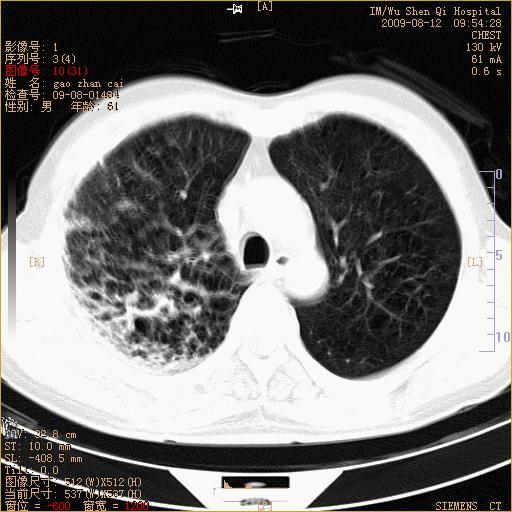

标题: CT21567:咳嗽,咳痰,发热半月余 [打印本页]

标题: CT21567:咳嗽,咳痰,发热半月余

1、右上肺继发性肺结核合并感染;2、肺气肿。

考虑支气管囊肿合并感染.

右肺间质纤维化右肺间质性肺炎

右肺上叶干酪性肺炎

右肺弥漫性间质性改变

考虑右肺间质性肺炎并右侧胸膜炎可能性大。

右上肺干酪性肺炎,肺气肿

考虑右肺支扩并感染可能,结核不除外,结核生化检查看看。

右肺门区占位待排(图片没有传完)

右肺间质性肺炎,肺气肿

考虑右肺结核, 右肺间质性改变,肺气肿。

支持右肺间质性肺炎。

右肺上叶支扩并感染,肺间质纤维化。

1)右肺上叶感染性病变;建议抗炎治疗后复查。2)肺气肿。

右肺上叶支扩并感染,肺间质纤维化,肺气肿,右肺门淋巴结肿大。建议抗炎治疗后复查。

支扩合并感染